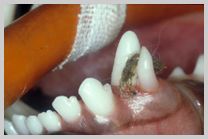

Teeth Destroyed by Disease

Teeth ruined by advanced caries, feline neck lesions etc.

should be considered for extraction.

Severe class 1 carie in occlusal pit

of 109